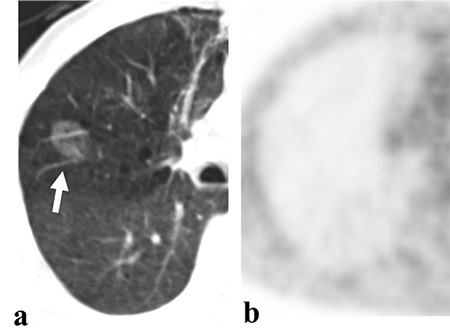

Methods: Tumors were divided into 2 groups according to CT appearance: Group 1: nodular-type tumor; group 2: mass- or pneumonic-type tumor. Unilateral and bilateral multifocal diseases were detected. Clinicopathological characteristics and PET/CT findings were compared between IMAs and LPAs, as well as between survivors and non-survivors.

Conclusions: Although CT images were useful for the differential diagnosis of LPAs and IMAs, SUVmax was not helpful for differentiation of these 2 groups. However, both 18F-FDG uptake and CT findings may play an important role in predicting prognosis in these patients.